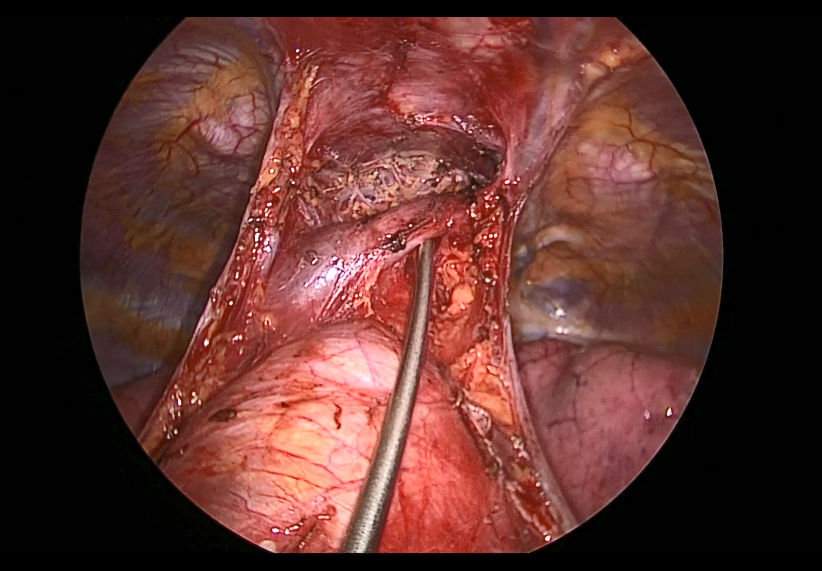

Pictured: Subxiphoid Uniportal Nonintubated Thymectomy

Joel Dunning, Enoch Akowuah, Emily Farkas - Subxiphoid Uniportal Nonintubated Thymectomy

Guseppe Aresu, Giacomo Argento - Adult Supravalvular Aortic Stenosis: Modified Three-Patch Aortic Root Reconstruction